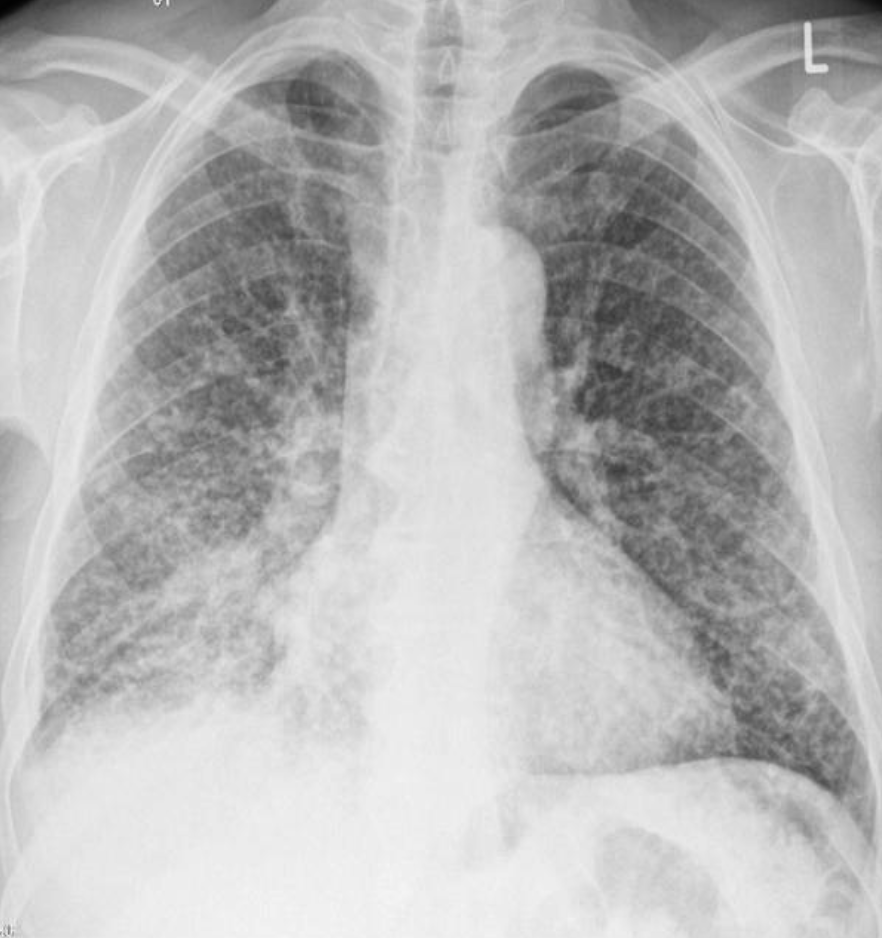

A 32 years old male presented with history of low grade fever, cough with sputum, sometimes blood stained. He has weight loss of 5 kg during this period. His chest X-Ray is shown ABOVE.

Describe the abnormality seen in the X-Ray?

- Cavitation and consolidation in the left upper lung

- bilateral Hilary lymphadenopathy

What is the likely diagnosis? Pulmonary TB

Mention 2 other investigations which you will advise?

- o Sputum culture and smear

- o IGRA

Mention 2 factors which increase the risk of this disease?

- HIV

- Chemotherapy

Mention 2 drugs used to treat this medical condition?

- o Rifampicin

- o INH (Isoniazid)